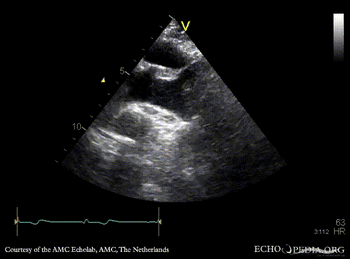

PLAX: dilated aortic root